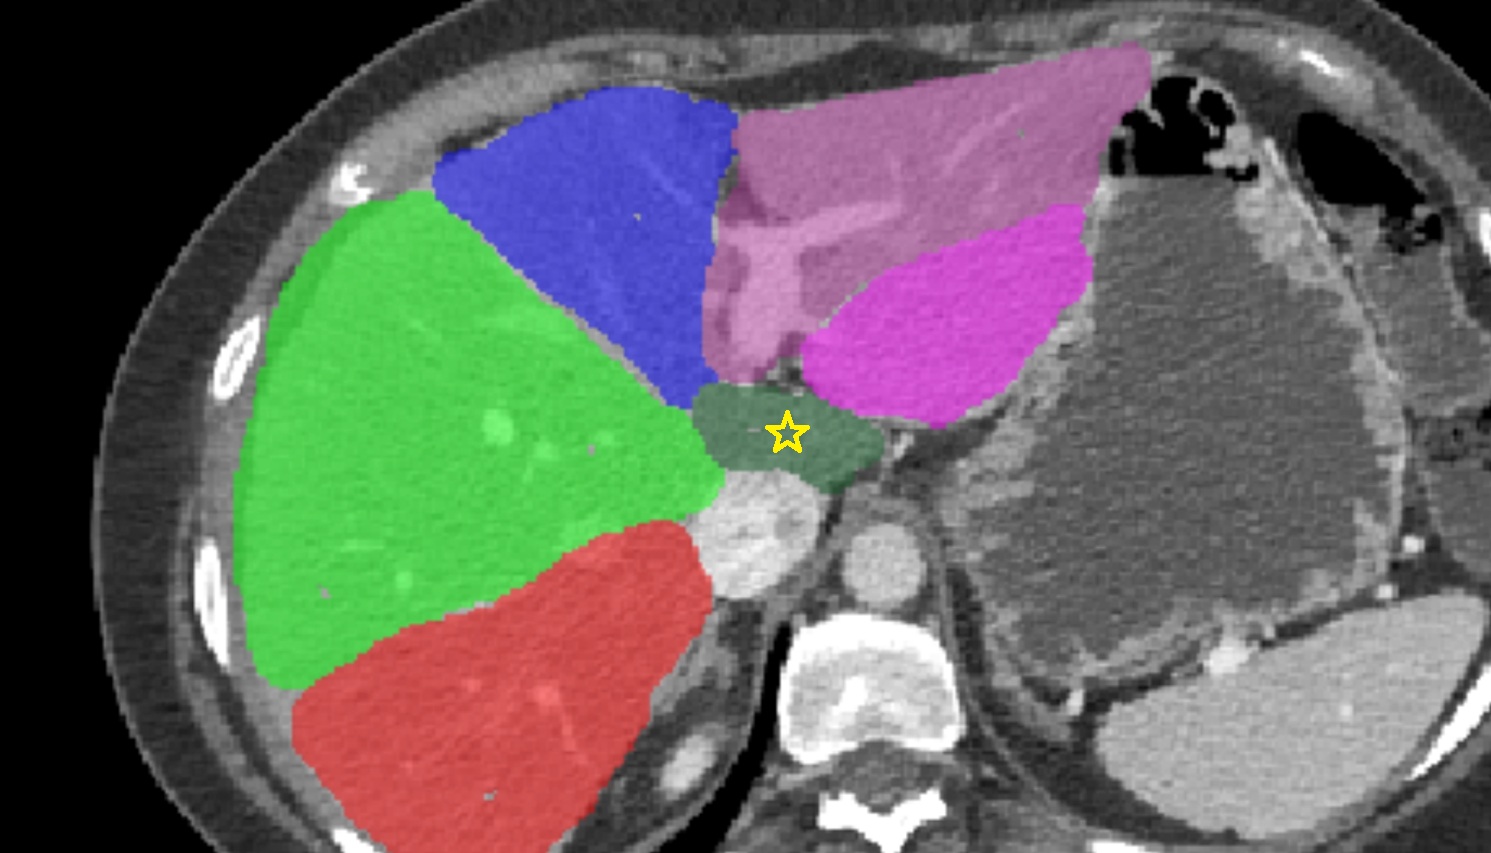

- Liver Segment I – Caudate lobe

- Liver Segment II – Left lateral superior segment

- Liver Segment III – Left lateral inferior segment

- Liver Segment IVa – Left medial superior segment

- Liver Segment IVb – Left medial inferior segment

- Liver Segment V – Right anteroinferior segment

- Liver Segment VI – Right posteroinferior segment

- Liver Segment VII – Right posterosuperior segment

- Liver Segment VIII – Right anterosuperior segment